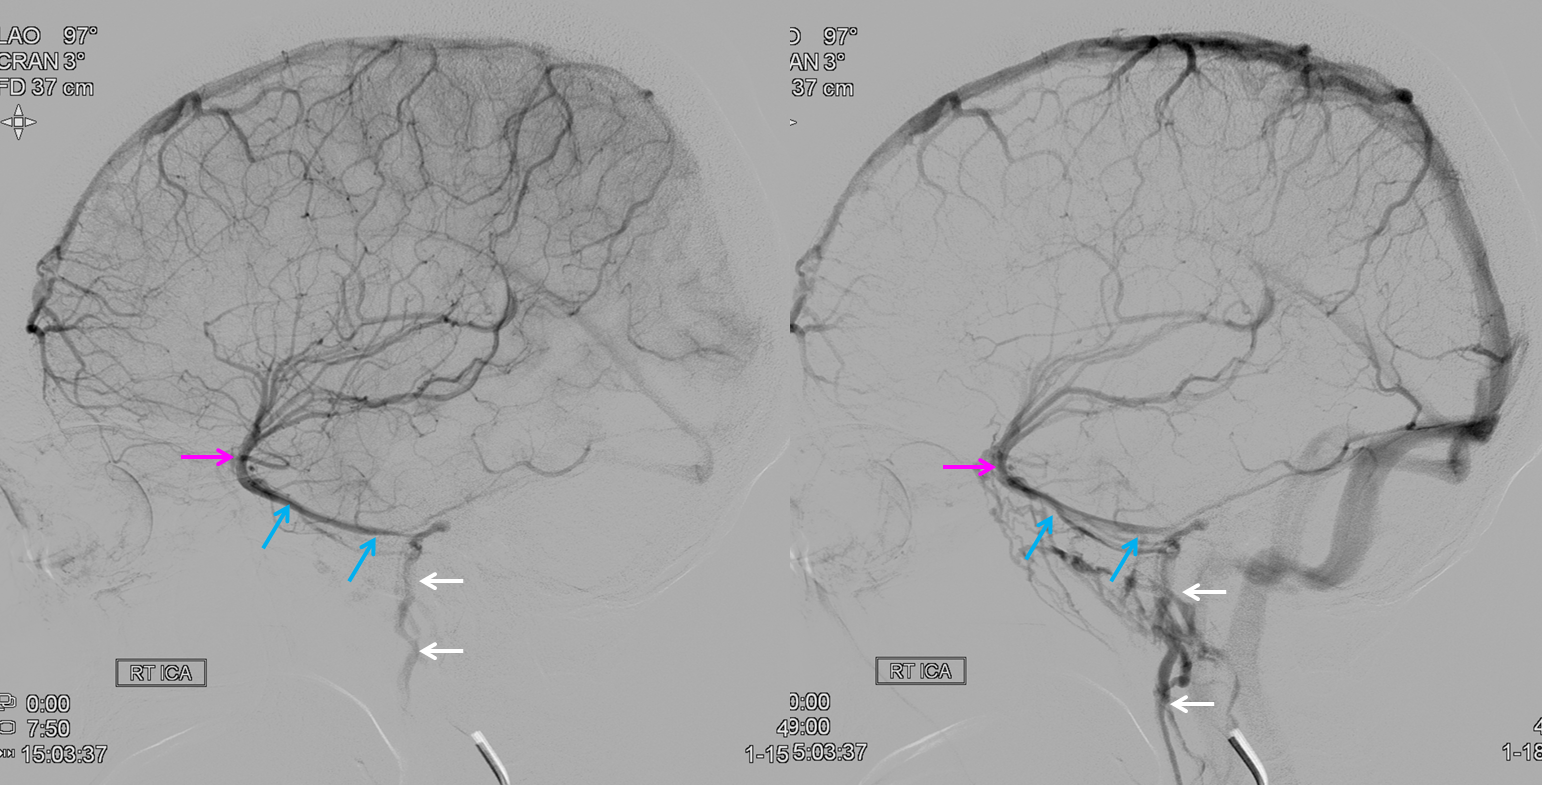

Sagittal Sinus Thrombosis — collaterals.

All of the above anatomic knowledge can become very useful in evaluation of venous thrombosis. Numerous collateral pathways develop in this setting attempting to compensate for the loss. The most dramatic cases usually involve the largest channel — the superior sagittal sinus. In this case, a man presented with what initially was thought to be vasculitis-related brain hemorrhage. Subsequent workup led to an angiogram, where sagittal sinus thrombosis with extensive trans-cerebral and trans-osseous emissary vein collateral channels was seen. In retrospect, these findings were present on the patient’s earlier contrast MRI. “Venovibe” or other contrast-enhanced MR venograms can very sensitive, particularly when interpreted with the appropriate index of suspicion. Noncontrast 2-D time of flight MRV I consider to be next to useless as a problem-solving technique. Any thin-slice postcontrast T1 study is vastly superior.